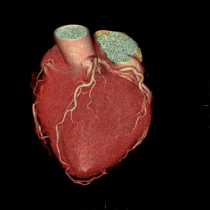

◆連載「激変の診断フロー」~虚血性心疾患(全5回)~バナーをアップしました!